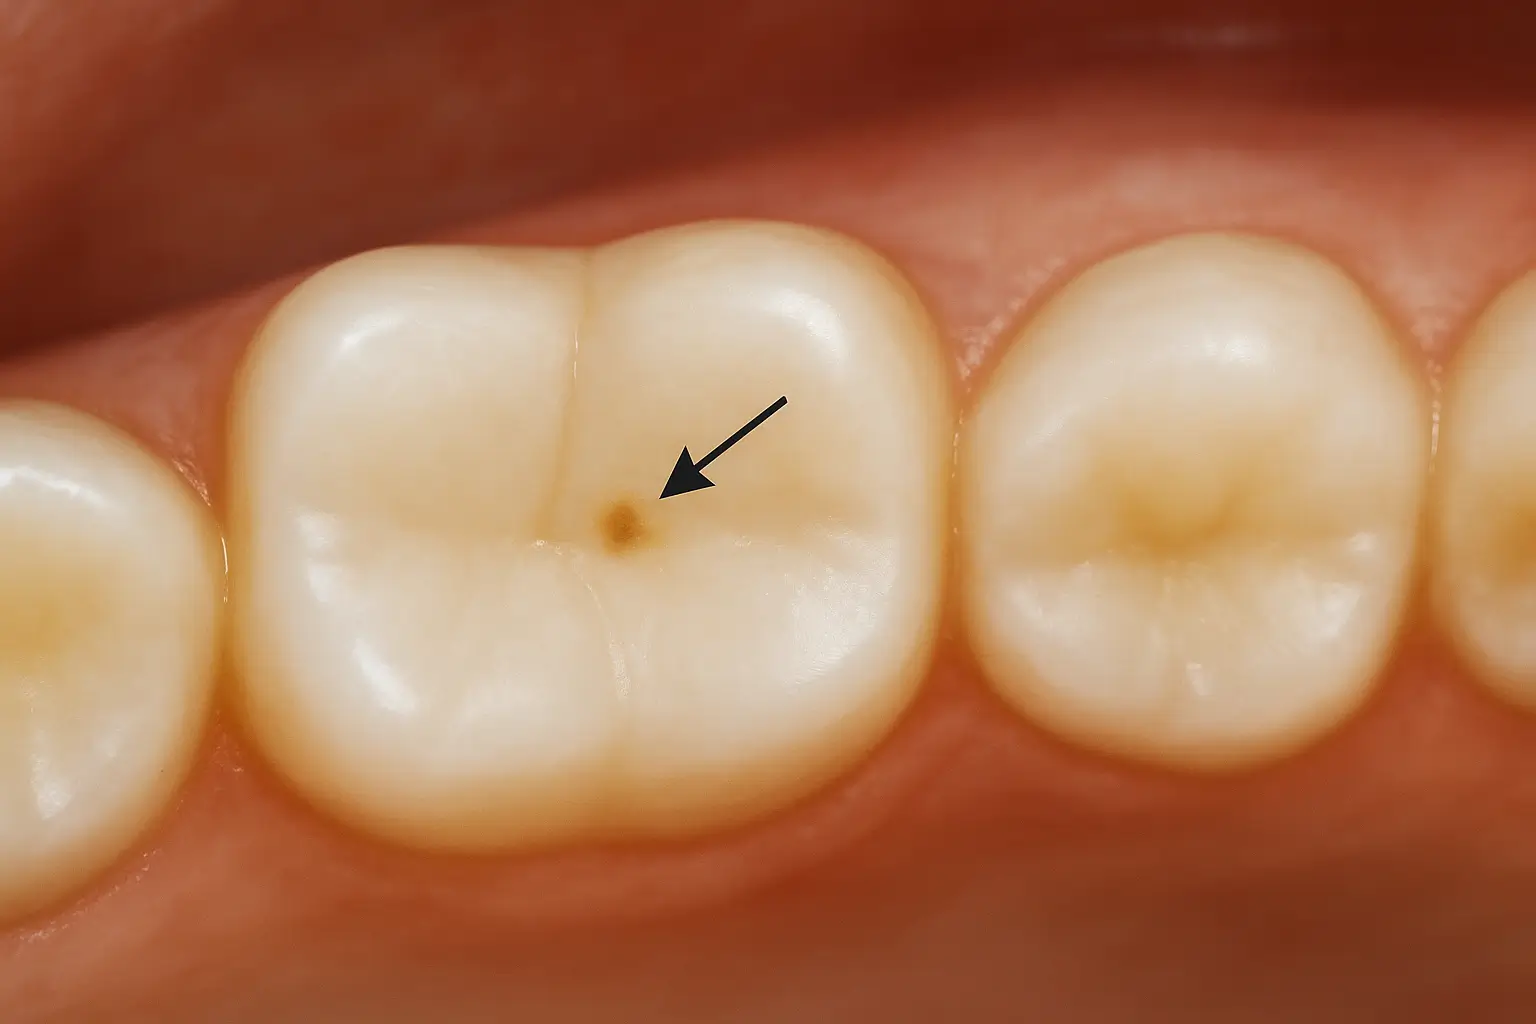

- بقع بيضاء طباشيرية: هذه هي أول علامة مرئية على فقدان المعادن من المينا.

- بقع بنية أو صفراء خفيفة: مع تقدم العملية، قد يتغير لون البقعة بسبب امتصاص الأصباغ من الأطعمة والمشروبات.

اشكال تسوس الاسنان البسيط وأماكن ظهوره الشائعة

- السطوح الماضغة (Occlusal Decay): الشقوق والحفر العميقة في الأضراس الخلفية هي مكان مثالي لتجمع الطعام والبكتيريا، مما يجعلها الموقع الأكثر شيوعًا للتسوس، خاصة عند الأطفال.